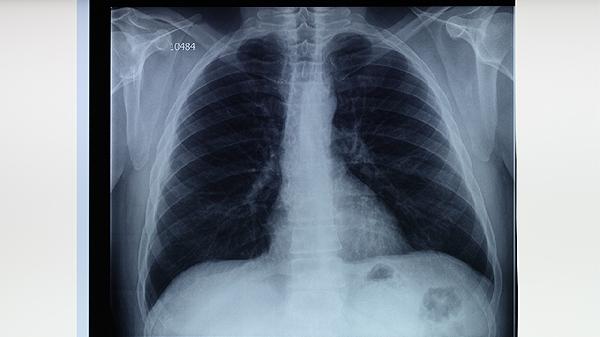

血行播散型肺結(jié)核可分為急性和慢性兩種。急性血行播散型肺結(jié)核起病急驟,表現(xiàn)為高熱、寒戰(zhàn)、呼吸困難等癥狀,胸片可見雙肺均勻分布的粟粒樣結(jié)節(jié)。慢性血行播散型肺結(jié)核癥狀相對(duì)較輕,但病程較長(zhǎng)。該類型肺結(jié)核需及時(shí)就醫(yī),治療方案包括鏈霉素注射液、乙胺丁醇片等抗結(jié)核藥物聯(lián)合使用。

繼發(fā)性肺結(jié)核是最常見的肺結(jié)核類型,多見于成年人。病變多位于肺尖或鎖骨下區(qū),可形成空洞。常見癥狀包括咳嗽、咳痰、咯血、盜汗和體重下降等。診斷需結(jié)合痰涂片檢查、胸部CT等。治療需長(zhǎng)期規(guī)范使用抗結(jié)核藥物,如利福噴丁膠囊、對(duì)氨基水楊酸鈉片等。